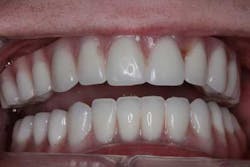

The maxillary arch was indexed first as there was support from the palate to reference position (anterior/posterior) (figure 20). Then the lower was put into position to gain proper vertical dimension and occlusion. It, too, was then indexed; both upper and lower were given to the lab technician to start the conversion process. Next, impression copings were placed (one arch at a time) and secured with paperclips; a full-arch PVS impression was taken and likewise sent to the lab (figures 21-23). Finally, after the conversion process was completed, the bridges were secured in place on the multiunit abutments, torqued to 15nCm, and covered. Bite was adjusted and follow-up care was arranged (figures 24-26).

We were done. Sara looked into the mirror and cried; extreme contentment and relief washed over her face. Our team assembled for a postsurgical photo before she was released (figure 27). The first time her parents saw her, they, too, were overcome with sentiment and the tears came again. Dr. John Holtzen and I walked back into the surgery center and smiled at each other. Words didn’t need to be spoken because Sara and her parents had said it all.

Next, Sara went shopping. She got her hair and makeup professionally done (figure 28) and then she smiled like she had never smiled before in front of a camera, radiating confidence and inner beauty that is without question, beyond words (figures 29-31).